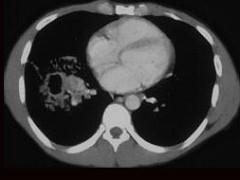

男,42岁,高热,寒战,咳嗽,胸痛1周左右,CT检查如图,选择最可能的诊断 ( )A、肺脓肿B、肺转移瘤C、肺癌D、肺囊肿E、肺结核

问题 男,42岁,高热,寒战,咳嗽,胸痛1周左右,CT检查如图,选择最可能的诊断 ( )

选项 A、肺脓肿 B、肺转移瘤 C、肺癌 D、肺囊肿 E、肺结核

答案 A